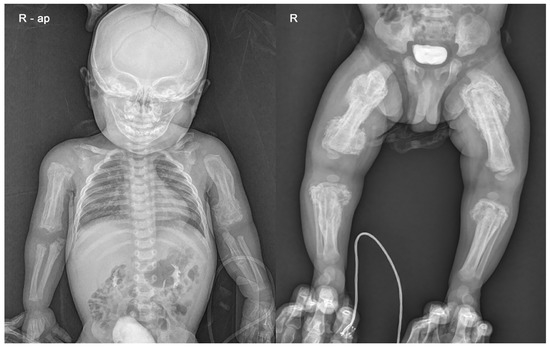

Skin lesions such as bruises or abrasions were not observed in the extremities, but an extensive periosteal reaction with transverse fractures was observed in both upper and lower long bones (Figure 2). There was no specific history of injury. Radiographs showed multiple fractures of both femurs, right tibia, and both ulna in various stages of healing. Spiral fractures were observed in the right tibia and right ulna (Figure 3).

Figure 2. Infantogram and radiograph showing extensive periosteal reaction with multiple fractures in both upper and lower long bones.